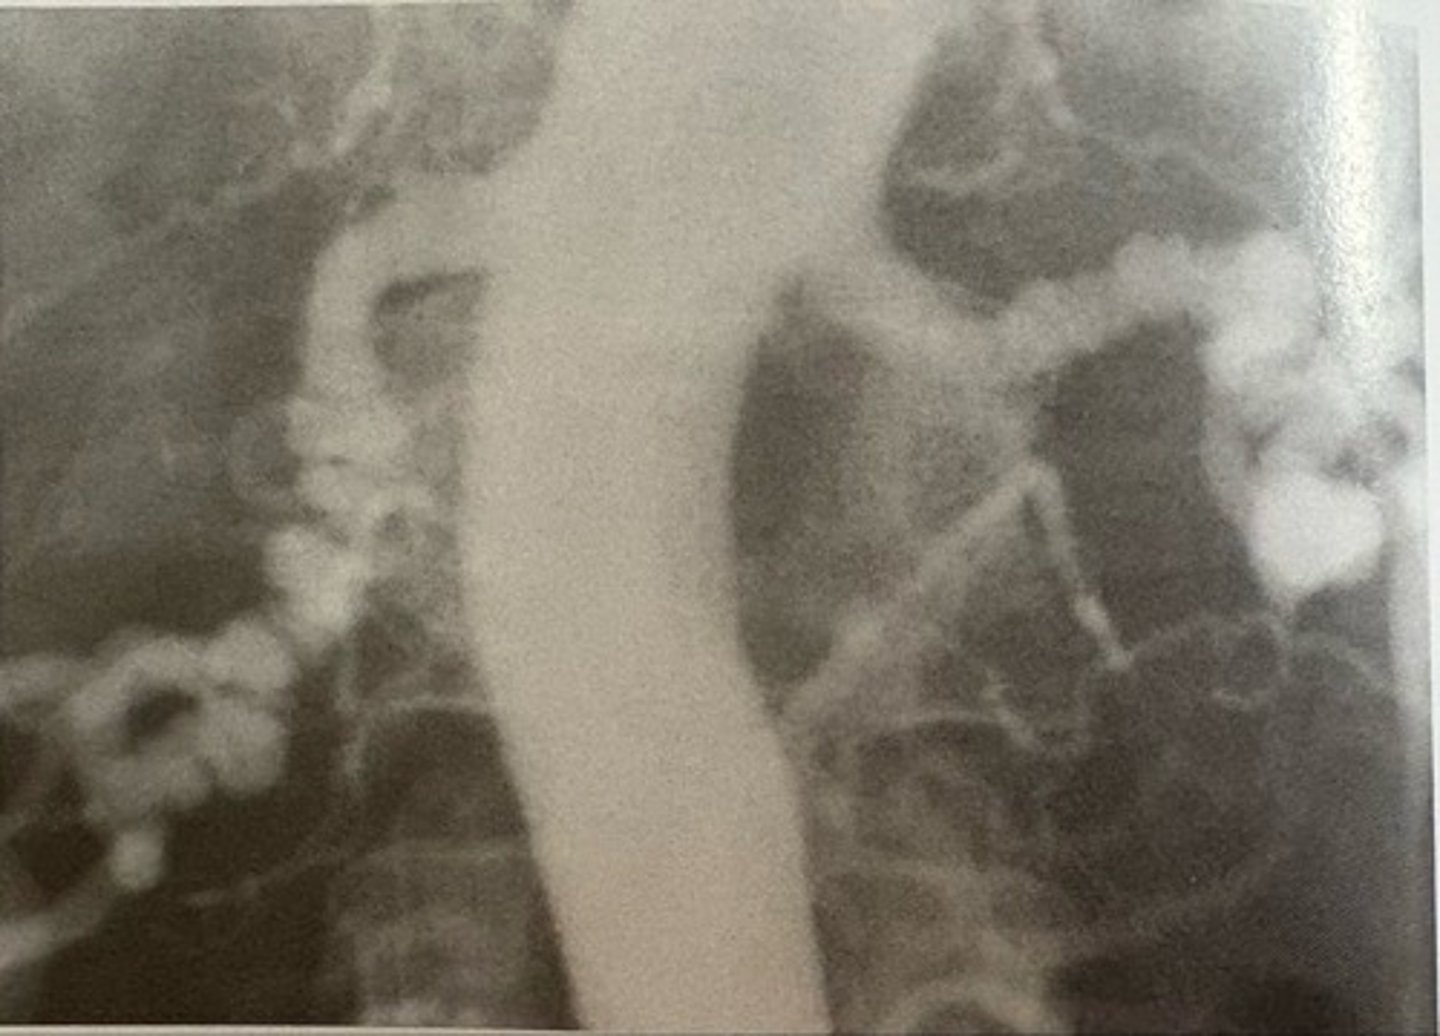

left coronary artery angiogram

what pathology is present?